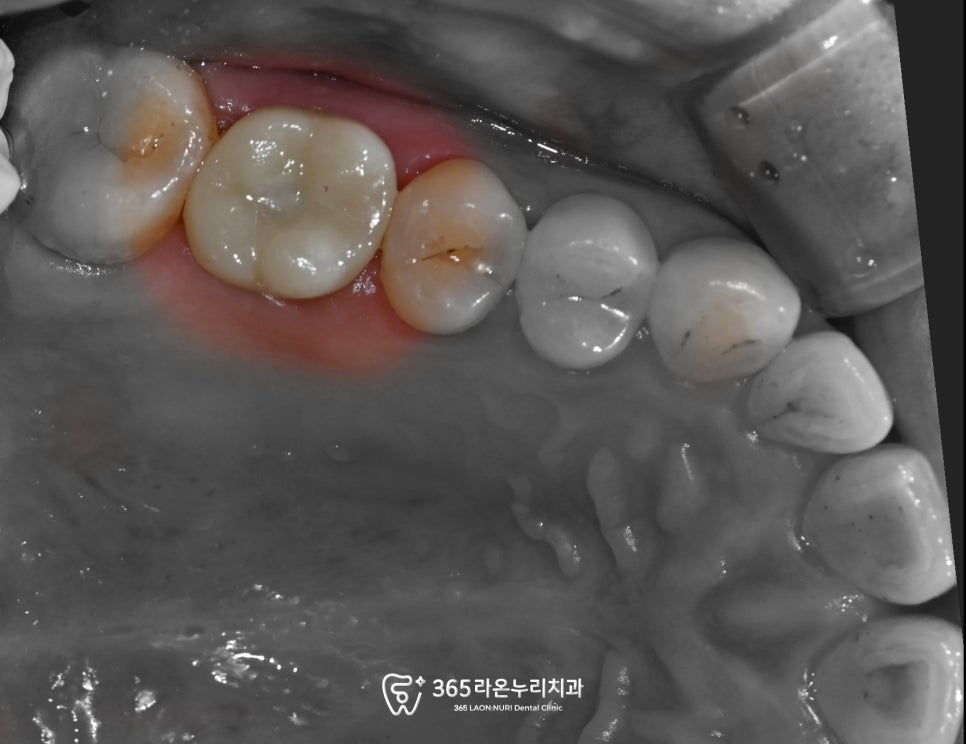

초진 구내 사진을 보면

광범위한 충치 때문에

치아가 깨진 모습을 볼 수 있었습니다.